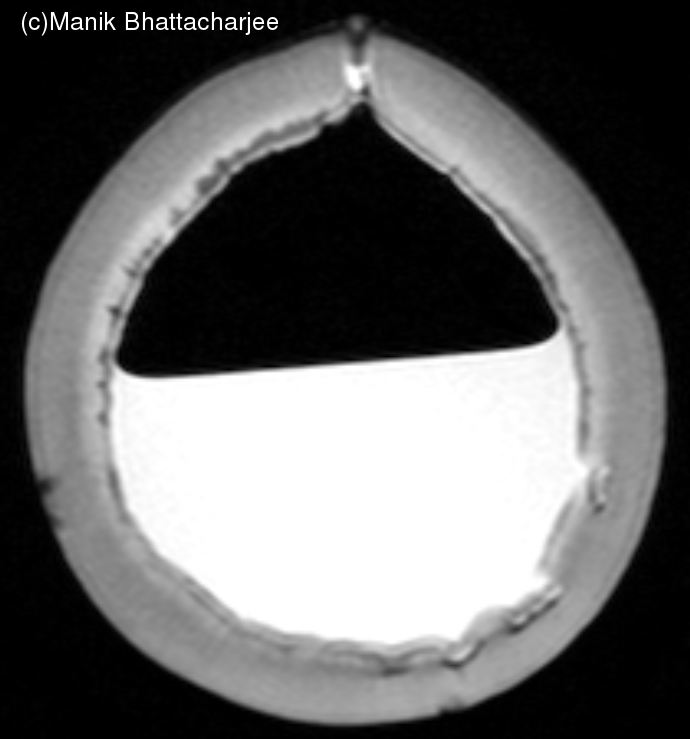

When trying to construct a head model for MRI studies, I did some experiments with coconuts.

Here are some images using BrainVisa/Anatomist for display of the acquisitions from a coconut still half full of juice.